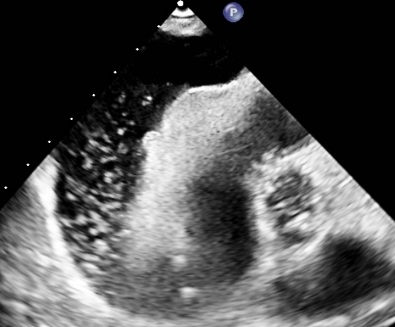

Microbubbles In the Pericardial Space: An Unusual Echocardiographic Finding

Hydropneumopericardium is a term used to describe accumulation of fluid as well as air in the pericardial space. Air or microbubbles in the pericardial space are rare findings typically associated with trauma, invasive procedures, or mechanical ventilation. Less common causes include malignancy, infection, and spontaneous erosion of adjacent structures. Early identification is important, as pneumopericardium can lead to tamponade and have a high mortality rate.

A 79-year-old woman with asthma presented with dyspnea, orthopnea, weight loss, and a right chest wall mass for 7 years. CT image revealed bilateral pleural effusions, a large pericardial effusion, and a right upper lobe soft tissue mass. Transthoracic echocardiography revealed a large pericardial effusion with unusual bright echo densities suggestive of microbubbles, raising concern for potential pneumopericardium. Pericardiocentesis was performed, yielding 400 mL of serous fluid. The drain remained in the place for approximately a week with persistent drainage that tapered slowly. The patient opted against getting a prophylactic pericardial window. Cytology reports came back positive for malignant effusion with suspected primary as malignant breast cancer, that is Estrogen Receptor and Progesterone Receptor positive. She was then started on Anastrozole and discharged to rehab with close follow up with oncology.

Pneumopericardium is most often related to trauma, barotrauma, or procedures such as pericardiocentesis, pacemaker placement, or esophagectomy. Less common causes include malignancy, tuberculosis, aspergillosis, and gastropericardial fistulae. Microbubbles in the pericardial space may be an early sign of air leakage, often preceding overt pneumopericardium. In our case, no communication with airways or gastrointestinal tract was identified on imaging, and no mechanical ventilation was used, ruling out barotrauma or fistulization. The presence of microbubbles may reflect localized necrosis or vascular invasion by tumor, leading to micro-air leak. Given the high mortality of unrecognized pneumopericardium and its potential for tamponade, early recognition of intrapericardial bubbles is critical. This case expands the differential diagnosis of this rare echocardiographic finding and highlights the importance of malignancy as an underlying etiology.